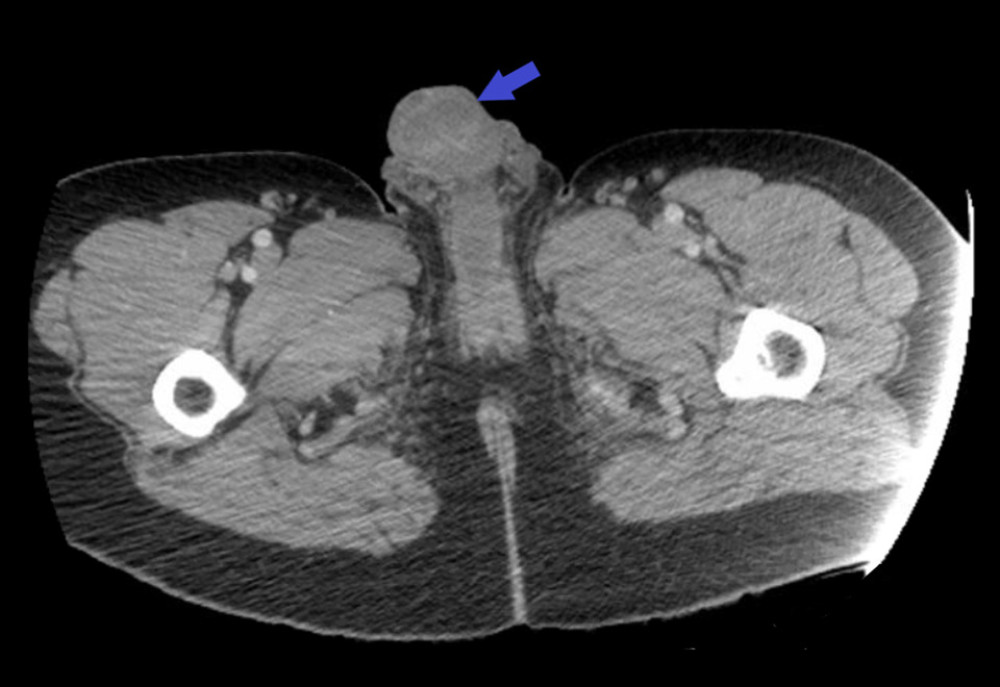

e Penile fracture with eggplant deformity. Download Scientific Diagram Eggplant Deformity penile fracture classically presenting with an 'eggplant deformity' where haemorrhage extends beyond the tunica albuginea. classic presentation includes report of a sudden “pop” or “snap” followed by pain, rapid detumescence, and. “eggplant deformity” or “aubergine sign” have been commonly used to describe the appearance of a fractured penis 6; physical exam findings may include edema, ecchymosis,. Eggplant Deformity.

Eggplant deformity the classic appearance of a penile fracture, with Eggplant Deformity the gross appearance is described as an “eggplant deformity,” which refers to the combination of localized. the diagnosis of a fractured penis is primarily based on clinical history and physical examination findings, including the classic. “eggplant deformity” or “aubergine sign” have been commonly used to describe the appearance of a fractured penis 6; classic presentation includes. Eggplant Deformity.